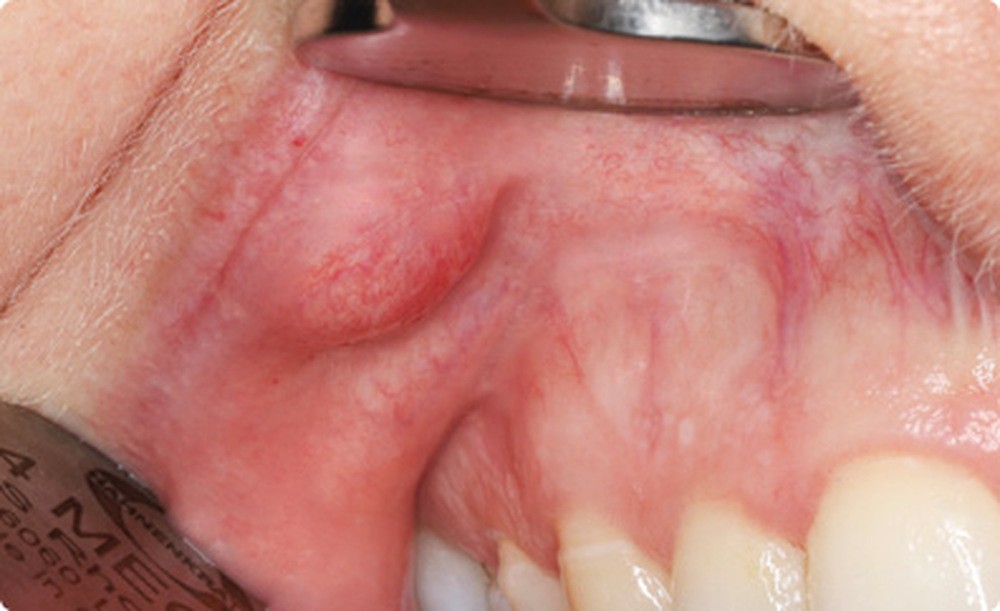

- Cette patiente avait une très bonne hygiène bucco- dentaire et présentait deux arcades dentaires indemnes de caries et de soins. Dans la lèvre supérieure droite, on palpait un nodule sous-muqueux, indolore, ferme, bien limité, mobile, arrondi, de 4 mm de diamètre. Lorsque la muqueuse était mise en tension, il prenait une couleur jaunâtre.